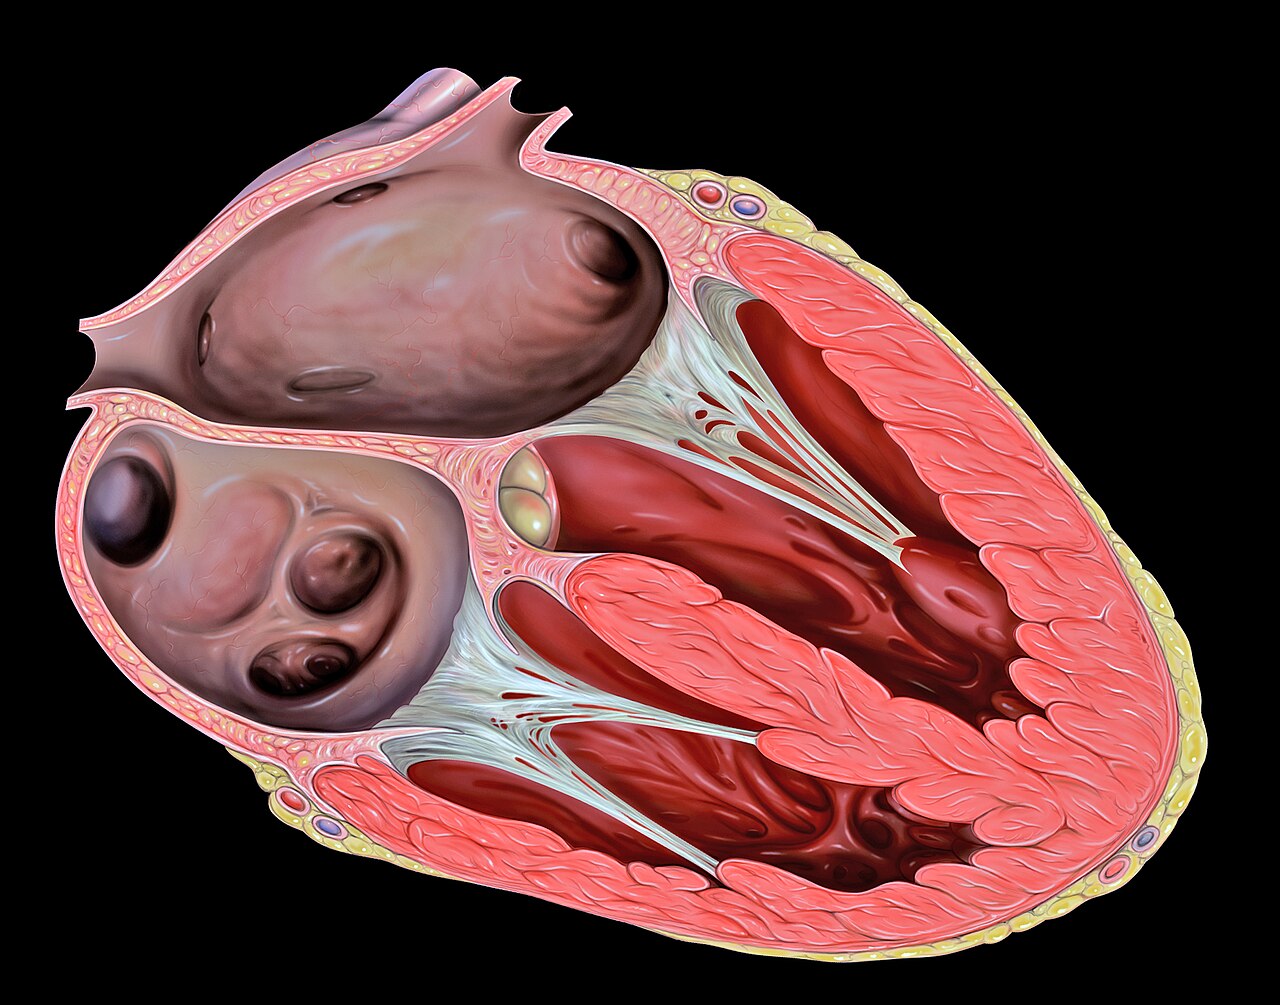

Cardiac phantom with myocardium, chambers, valves, and coronary arteries

AI-generated comprehensive cardiac phantom with all four chambers, valves, coronary arteries, great vessels,...